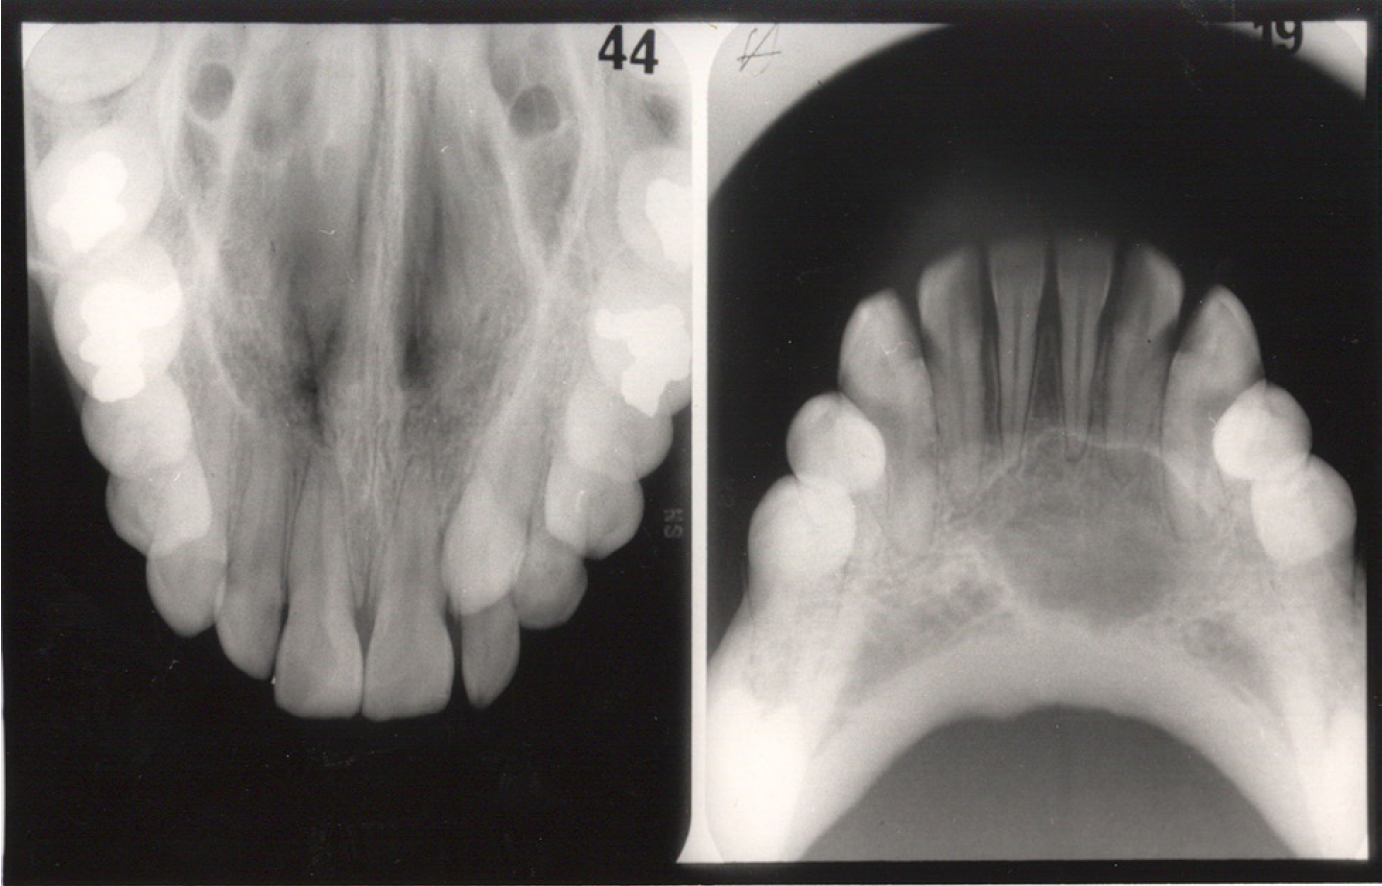

Figure 3 - Occlusal Images

Figure 3

Occlusal radiography is a supplementary radiographic examination designed to provide a more extensive view of the maxilla and mandible.

The occlusal image, as seen in Figure 3, is very useful in determining the buccolingual extension of pathologic conditions and provides additional information as to the extent and displacement of fractures of the mandible and maxilla. Occlusal radiographic images also aid in localizing unerupted teeth, retained roots, foreign bodies, and calculi in the submandibular and sublingual salivary glands and ducts. It should be noted that when imaging soft tissues, exposure time needs to be appropriately reduced.